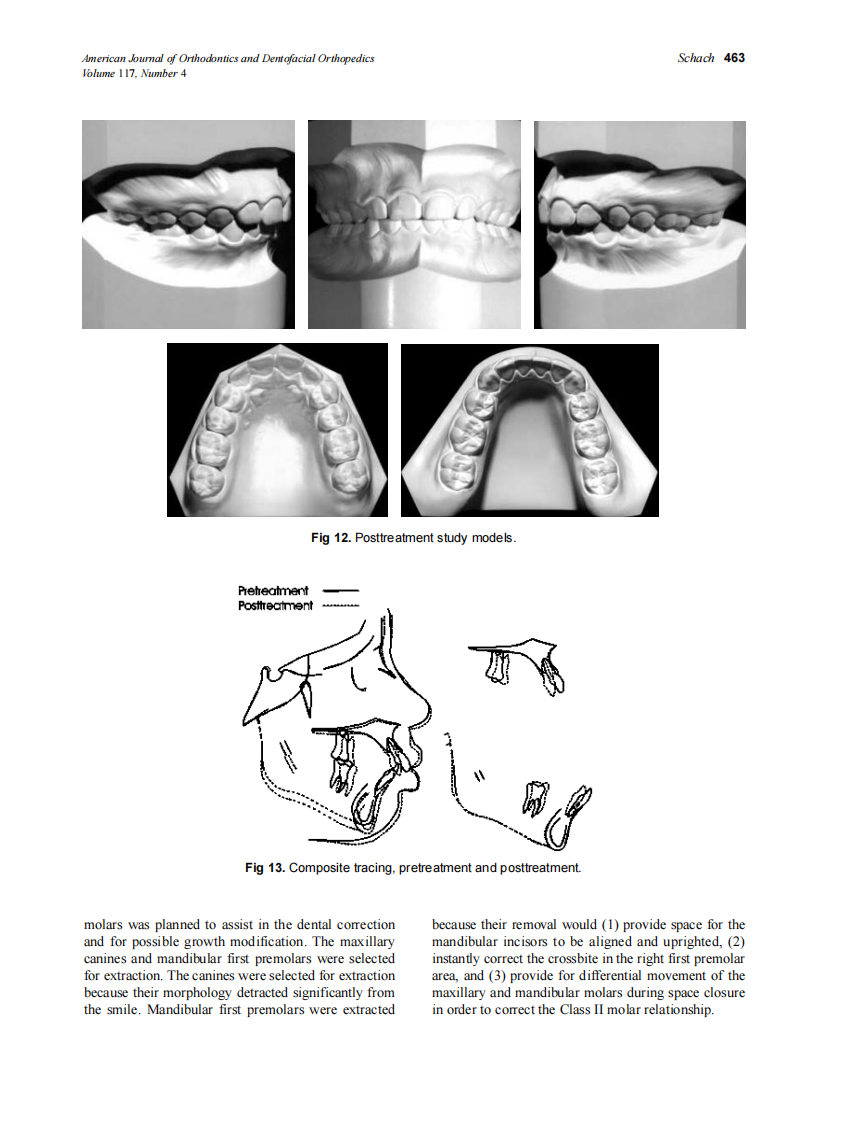

2000_117_4_459_464_Schach.pdf